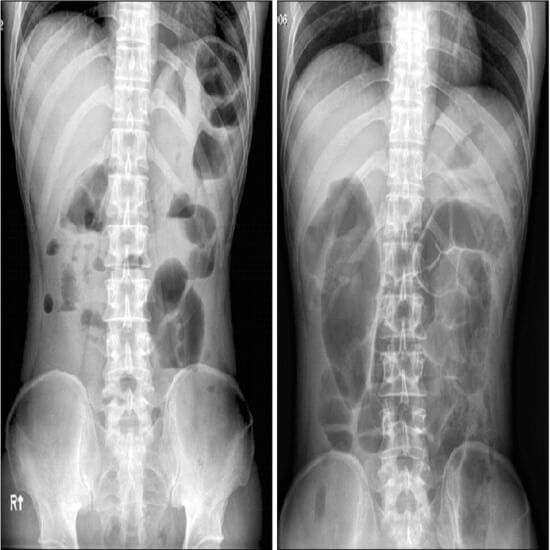

Doctors often ask for this kind of abdominal X-ray when they think a patient has a bowel obstruction or wants to see how much air and fluid is in a swollen bowel.

An X-ray of the abdomen in an erect position can aid in identifying a variety of abdominal problems. X-rays are commonly used to diagnose the following conditions:

• Abnormal gas pattern or bowel blockage

• To find organs with abnormal size or shape.

• To detect the formation of aberrant masses.